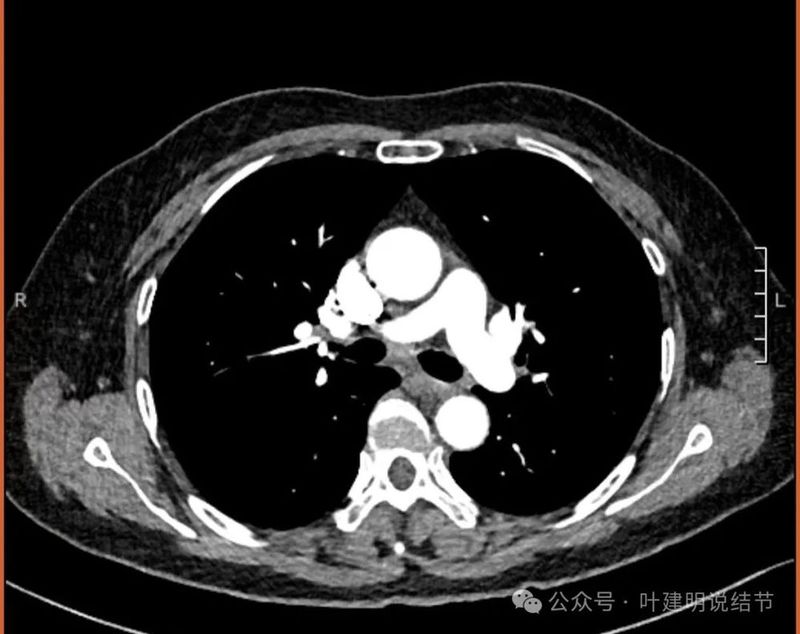

外院增强CT影像:

左下病灶混合密度,实性成分明显,但收缩力不强,磨玻璃成分非常明显,而且轮廓与边界清楚,灶内有小空泡征,表面有分叶,灶内有多支血管走行。

纵隔窗见有明显实性成分,磨玻璃成分不可见,走行血管也明显。

纵隔与肺门没有见到显著增大融合要考虑转移的淋巴结。